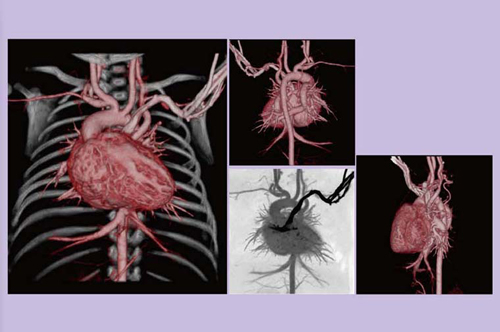

図3は,胸痛の精査で来院した器質的狭窄のない心拍数47bpmの症例で,スキャンタイム0.29秒,被ばく線量は0.97mSvであった。冠動脈が十分評価できており,胸痛のスクリーニングとしても有用と思われる。

図3 68歳,男性,胸痛精査

図4は,ステント留置のフォローアップで,スキャンタイム0.3秒,被ばく線量は1mSvであった。かなり強い石灰化がある症例であったが,ステント内腔が明瞭に描出できている。

図4 74歳,男性,ステント留置フォローアップ

図5は,冠動脈バイパス術(CABG)で,グラフトを4本使用している症例のフォローアップであるが,アーチファクトもなく,十分評価可能な画像が得られている。

図5 78歳,男性,CABGフォローアップ